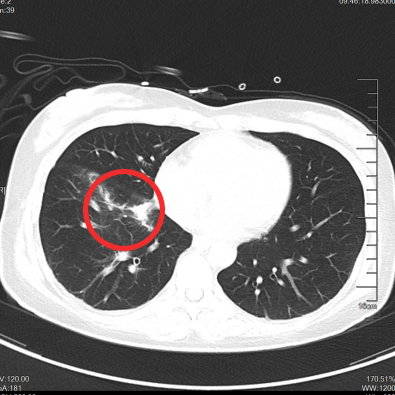

▲治疗前

▲治疗后1月

▲治疗后2年半

我们给这位年轻患者口服了靶向药

短短一个月

患者肺部和脑部肿瘤就出现明显退缩

随访至今

肺部、颅内、可见淋巴结、腹腔等

多处病灶完全缓解

患者日常生活无异于常人

我们对她能生存5年,甚至10年充满信心